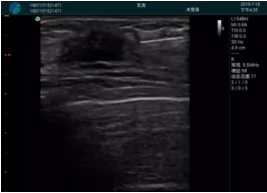

腺體內(nèi)部清晰顯示一低回聲塊影,形態(tài)不規(guī)則,邊界模糊,邊緣呈毛刺狀,內(nèi)部見砂礫樣鈣化

M20引導(dǎo)下穿刺活檢術(shù)

M20引導(dǎo)下平面內(nèi)穿刺取出的腫塊組織

M20查看:囊內(nèi)回聲均勻,邊界清晰,囊壁光滑

M20引導(dǎo)抽吸術(shù)后囊腫消失,原區(qū)域空腔形成,脂肪層與腺體層架構(gòu)發(fā)生改變

超聲以操作簡單、定位準(zhǔn)確、實時顯像、費用低廉等優(yōu)勢,而成為麥默通乳腺活檢治療乳腺腫塊最常見的引導(dǎo)手段,已逐步在各大醫(yī)院開展此類手術(shù)。

2、超聲的可視化操作,能準(zhǔn)確的顯示病灶的位置、最大徑,選擇合適的刀具,決定切口的位置和方向,避開血管、減少出血危險并實時觀察乳腺病灶的切割情況,避免造成腫塊組織殘留